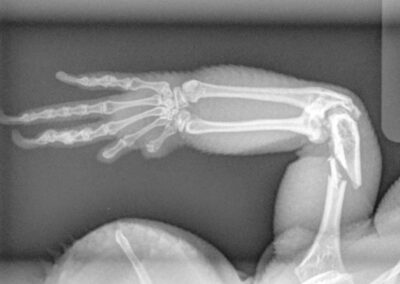

Fracture Repair

We provide surgical fracture repair for many types of broken bones. Treatment plans are individualized based on the location and complexity of the fracture, your pet’s age and size, and overall health.

Radius Fracture Before #1

Radius Fracture Before #2